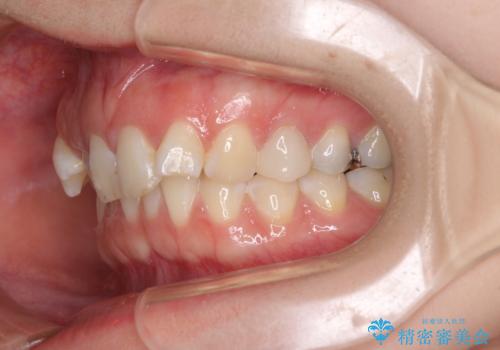

- 前歯の歯列不正を気にして来院された患者様です。

インビザラインでの矯正治療を希望されていましたが、奥歯の咬み合わせがインビザライン単独では改善困難と判断されたので、補助装置を併用することとしました。

まずは裏側の装置やワイヤー矯正を用いて歯列幅の狭い上顎を側方に拡大しつつ全体を後方に移動させ、その後インビザラインにて歯列を整えることとしました。